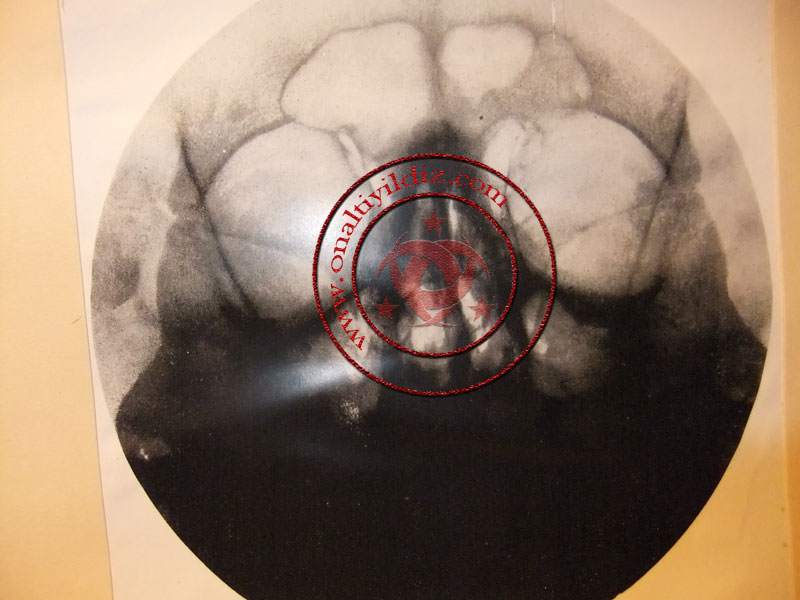

Ben ise ne olup bittiğini anlamaya çalışıyordum. Göz ucuyla Osman Baba’nın sayfalarını karıştırdığı esere bakıyordum. Gördüğüm kadarı ile Fransızca yazılar ve röntgen resimleri vardı. Daha önce örneğini hiç görmediğim bir şeydi bu.

Osman Baba: “Eren evladım çok şükür bu emanet bugün bize ulaştı. Nasibin varmış ki bugün geldi. Ben bunun varlığını biliyordum ama daha önce hiç görmemiştim. Bursa’daki emanetçideydi. Sabah senden ayrıldıktan sonra ona uğramıştım. Burada olduğumu biliyorlardı. Bu yüzden bu eseri kullanmamız için gönderdiler. Biraz sonra da alacaklar. Sen şimdi bunun resimlerini çek, sonra bu çok önemli bilgileri ifşa edelim inşallah,” dedi.

Ben hemen resimleri çekmeye başladım. Yaklaşık 40-50 sayfalık kitaba benzer bu eserin resimlerini çektim.

Osman Baba kitaba benzer bu katalogu alarak çantasına koydu: “Böyle ortalıkta durmasın. Ne olur ne olmaz. Eren evladım, sanırım merak ediyorsun, bu nedir? diye. Haklısın, şimdi anlatacaklarımı iyi dinle. Yakın tarihin en önemli olaylarından birini, Hitler’in nasıl hazırlandığını ve İsrail’in nasıl kurulduğunun ipuçlarını vereceğim sana. Hitler bir proje olarak nasıl hazırlandı ve Hitler’in üzerinde yapılan tıbbi deneyler neler? Elimizdeki bu eser, Hitler’in sağlığı üzerinde nasıl oynandığını bizlere anlatmaktadır,” dedi ve anlatmaya başladı.

Hitler, Fransa’da bir klinikte basit bir hadiseden dolayı tedavi edilmişti. Dişleri ile ilgiliydi bu tedavi. İşte ne olduysa bu tedaviden sonra olacaktı

Bundan sonra kod adı “ayakkabı” olan bir operasyonla diş tedavisi bahanesi ile Hitler’in beynine yüksek miktarda radyasyon verildi. Bu alanda çalışan uzmanlar bilir ki, beynin belli bölgesine yüksek miktarda radyasyon verirsen, yarı deli kişilik halini alıyor, düşünce bozukluğu baş gösteriyor ve dayanılmaz kalıcı ağrılar oluşuyordu.

Konumuza dönecek olursak; 1936 yılında üstad mason derecesinde olan ve konusunda uzman doktor, Hitler’in üzerinde yaptığı uygulamaları/tıbbi deneyleri özel bir dosya olarak hazırlamış ve tarih atarak Fransa gizli teşkilatına teslim etmiştir. Teşkilat binasında bulunan kütüphanede bu dosya/kitap gizlenmiştir. Ele geçirildiğinde çoğu kimse bunun Hitler’e ait olduğunu bilememiştir. Bu sırrı, sadece 9 kişi bilmektedir. Hatta, geçtiğimiz günlerde Fransa Milli Arşivinde, tespit edilen bir kartta, Hitler'in gençlik yılları hakkında bilgi bulundu haberleri yapılmıştır.

Hitler’in üzerinde radyografik uygulamalar yapılmıştır. Bilindiği gibi Fransa’da radyasyonun insan üzerindeki etkilerine dair önemli çalışmalar vardır.